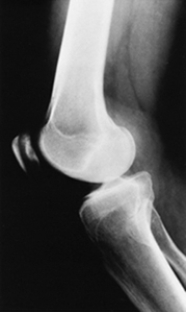

Which of the following imaging techniques illustrated in the pictures would be the most efficient to discover if there is a loose body within a joint?

Q15: Which of the following imaging techniques illustrated

Q17: Which of the following imaging techniques illustrated